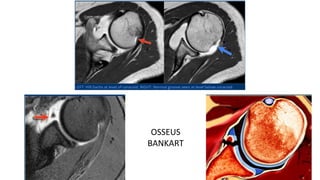

oFindings :

• Bankart lesion - may occur in conjunction with traumatic anterior instability

OSSEUS

BANKART